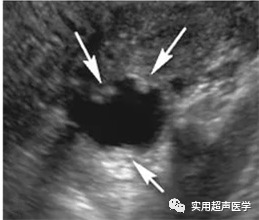

宫颈炎通常在超声检查中隐匿,可通过直接观察和培养进行诊断。子宫内膜炎在超声成像上表现为子宫内膜模糊增厚,子宫内膜通常血管极强。子宫内膜腔可能因液体、出血甚至空气而扩张,超声检查以回声灶和病灶后阴影为特征。输卵管或卵巢受累是盆腔炎性疾病的标志,可导致各种超声检查结果。输卵管炎表现为输卵管轻度增厚和充血和输卵管周围炎症。在超声检查上,这些变化导致突出或粗管,因此更容易看到,并且通常在彩色多普勒成像中观察到充血。由于炎症或感染,周围盆腔脂肪的回声和血管增加是常见的。可能存在少量邻近的复合游离液,卵巢可能出现增大和水肿,外观类似于多囊卵巢疾病。

输卵管轻度增厚和充血和输卵管周围炎症

输卵管炎症彩色多普勒显示周围血管增多